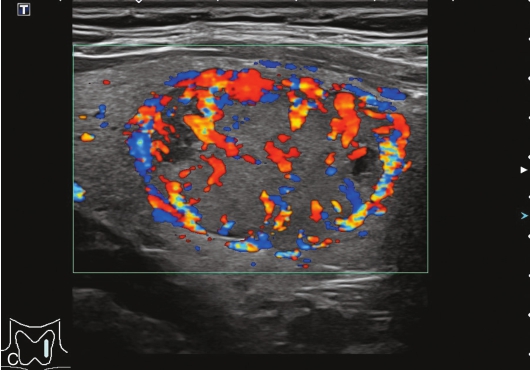

甲状腺形态基本正常,甲状腺实质回声稍增粗,分布尚均匀,甲状腺包膜尚光滑。甲状腺两叶内见多发结节,较大者位于左叶上极,呈类椭圆形,边界清楚,形态规则,纵横比<1,内部回声均匀,未见钙化,后方回声稍增强。CDFI显示左叶较大结节边缘可见丰富的条状血流信号,内部可见条状、点状血流信号,见图1-3-7。

图1-3-7 结节性甲状腺肿常规超声表现

A.常规超声图像;B.CDFI超声图像

甲状腺左叶上极较大结节增强早期呈稍高增强,自结节外周向中央灌注,增强晚期呈等增强,结节内部可见不均匀低增强区,见图1-3-8、ER1-3-4。

图1-3-8 结节性甲状腺肿超声造影图像

ER1-3-4 结节性甲状腺肿的超声造影

结节性甲状腺肿超声造影表现为病变多与周围正常甲状腺组织呈同步等或高增强,增强多较均匀,伴有囊性变者,内部可见无增强区,增强后结节边界清,周边可见环状增强,增强晚期呈等或稍高增强,也可呈稍低增强。

多早于周围正常甲状腺组织增强,从周边向中心快速充盈,呈均匀性高增强,增强后结节边界清,形态较规则,周边亦可见环状增强。

造影后结节大多呈同进或慢进,以不均匀性低增强多见,也可呈等或高增强,增强后结节边界不清,形态不规则,增强晚期可呈低增强或等增强。

图1-3-10 结节性甲状腺肿超声造影图

A.增强早期结节呈同步不均匀性等增强;B.增强晚期呈不均匀性低增强